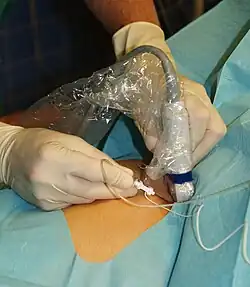

Déroulement typique de la reconstruction du ligament croisé antérieur

L'exemple présenté ci-après décrit le déroulement de la reconstruction du LCA par transplantation autologue de tendons semi-tendineux et gracile. Jusqu'aux années 1980, l'opération ouverte classique du LC était accomplie selon le procédé mis au point par Erwin Payr (de). Depuis, presque toutes les reconstructions de LC sont faites de façon peu invasive par arthroscopie[190],[266]. Ce n'est qu'exceptionnellement, par exemple pour des blessures très complexes du genou, que l'on pratique une opération ouverte.

Arthroscopie

L'opération proprement dite commence par l'introduction de l'arthroscope dans le genou du patient. Ceci permet de confirmer définitivement le diagnostic de rupture de LC. Les autres blessures, en particulier celles des ménisques, peuvent être soignées avant la reconstruction du LC.

Prélèvement du transplant

Le premier temps de l'opération est le prélèvement du transplant. Une incision d'environ 4 cm dans la peau sur la partie interne de la tête du tibia, au-dessus de la «patte d'oie» permet le prélèvement successif sur les tendons semi-tendineux et gracile. Les prélèvement sont faits sur les deux tendons avec un « couteau à tendon », et ont une longueur d'environ 28 cm. Ils sont pré-tendus avec un dispositif spécial, et cousus ensemble en un cordon multiple, par exemple quadruple. La longueur du transplant est alors de 7 cm, avec un diamètre d'environ 7 mm. Le transplant est alors cousu au moyen d'un fil spécial dans les deux trous internes d'un disque ovale à quatre trous (endobouton). Ce fil spécial n'est pas résorbable.

Élimination des restes de ligament croisé et percement des canaux osseux

Les restes du LCA rompu sont éliminés sous arthroscopie. Pour cela, on utilise un outil motorisé de découpe et d'aspiration. À l'aide d'un appareil à positionner, la position pour le percement d'un canal à travers la tête du tibia est déterminée, et le trou est fait. La même procédure est appliquée au percement à travers le fémur. Ce canal se rétrécit vers le haut et a une longueur d'environ 35 mm. La partie plus large de ce canal est destinée à recueillir le transplant, la partie étroite à faire passer l'accrochage du transplant.

Enfilage du transplant

Le transplant est inséré au moyen de deux fils de traction du bas vers le haut dans les trous percés. Au moyen d'une vis creuse, le transplant est fixé au fémur. L'extrémité sortant du canal du tibia est pré-tendue et fixée par coincement avec une vis d'interférence (vis delta). Puis les orifices opératoires sont recousus, en laissant un drain aspiratif. La durée de l'opération est environ de 45 à 90 min.

Après l'opération

Il est décisif pour la reprise fonctionnelle de placer le membre inférieur directement après l'opération en position étendue. Cette position doit durer 24 heures. Elle évite un déficit d'élongation post-opératoire, qui se forme souvent et peut nécessiter pour son élimination des semaines de traitement physiothérapique. Le lendemain de l'opération, on enlève habituellement les drains des ouvertures au genou. La jambe opérée ne peut être que légèrement chargée pendant les cinq semaines suivant l'opération, afin que les transplants puissent s'enraciner dans les os. Pour protéger le transplant sensible pendant cette période, on utilise une orthèse du genou. La rééducation peut d'habitude commencer après cinq semaines.